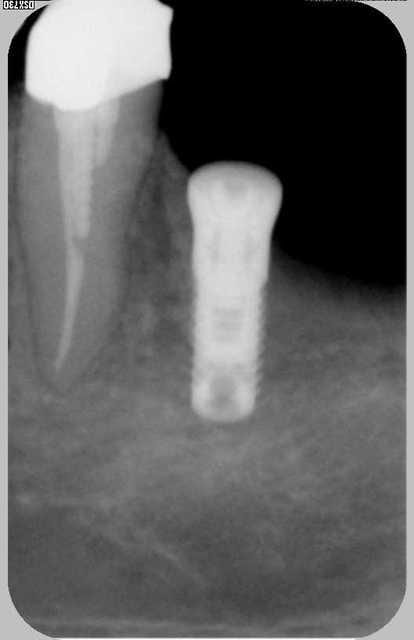

dans le même esprit voila un cas que j'ai réalisé il y à maintenant 5 ans .

mise en place d'un 4*10 en position de 36 lors du forage légère félure de la corticale vestibulaire par blocage du forêt de 2.8

j'ai mis en place l'implant et la suite parle d'elle même...

j'ai alors décidé de le mettre en fonction quand même et au final cinq ans après je n'ai vraiment aucun regret